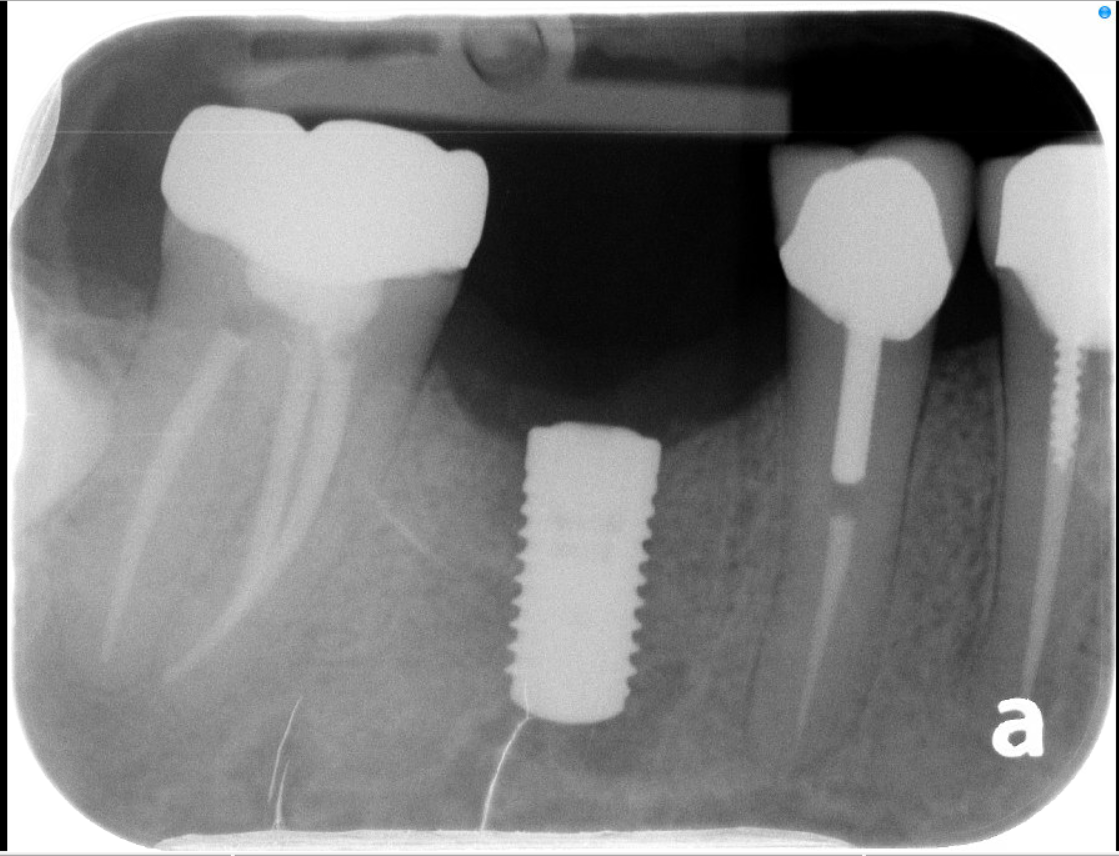

2. "All-on-X" Full-Arch Restoration

For patients who are missing most or all of their teeth in an arch, the All-on-X protocol (often All-on-4 or All-on-6) is a life-changing solution. Instead of one implant per tooth, we strategically place a specific number of implants (the "X") to support a full bridge of teeth.

A. Hybrid Prosthesis (Fixed)

This is the "gold standard" for permanent tooth replacement.

• How it works: The prosthetic teeth are screwed directly onto the implants.

• Experience: It is non-removable by the patient. It feels the most like natural teeth, offers maximum biting power, and does not cover the roof of the mouth.

Stability: High. It stays in 24/7 and is cleaned just like natural teeth (with specialized flossing tools).

1. 3D Imaging & Planning: We use CT scans to evaluate bone density and plan the exact placement of each implant.

2. Surgical Precision: Our periodontist performs the surgery in the comfort of your home office.

3. Integration (Osseointegration): We allow a healing period for the bone to fuse with the implant.

4. Final Restoration: Your general dentist takes over to design and fit your final crown, hybrid, or overdenture.